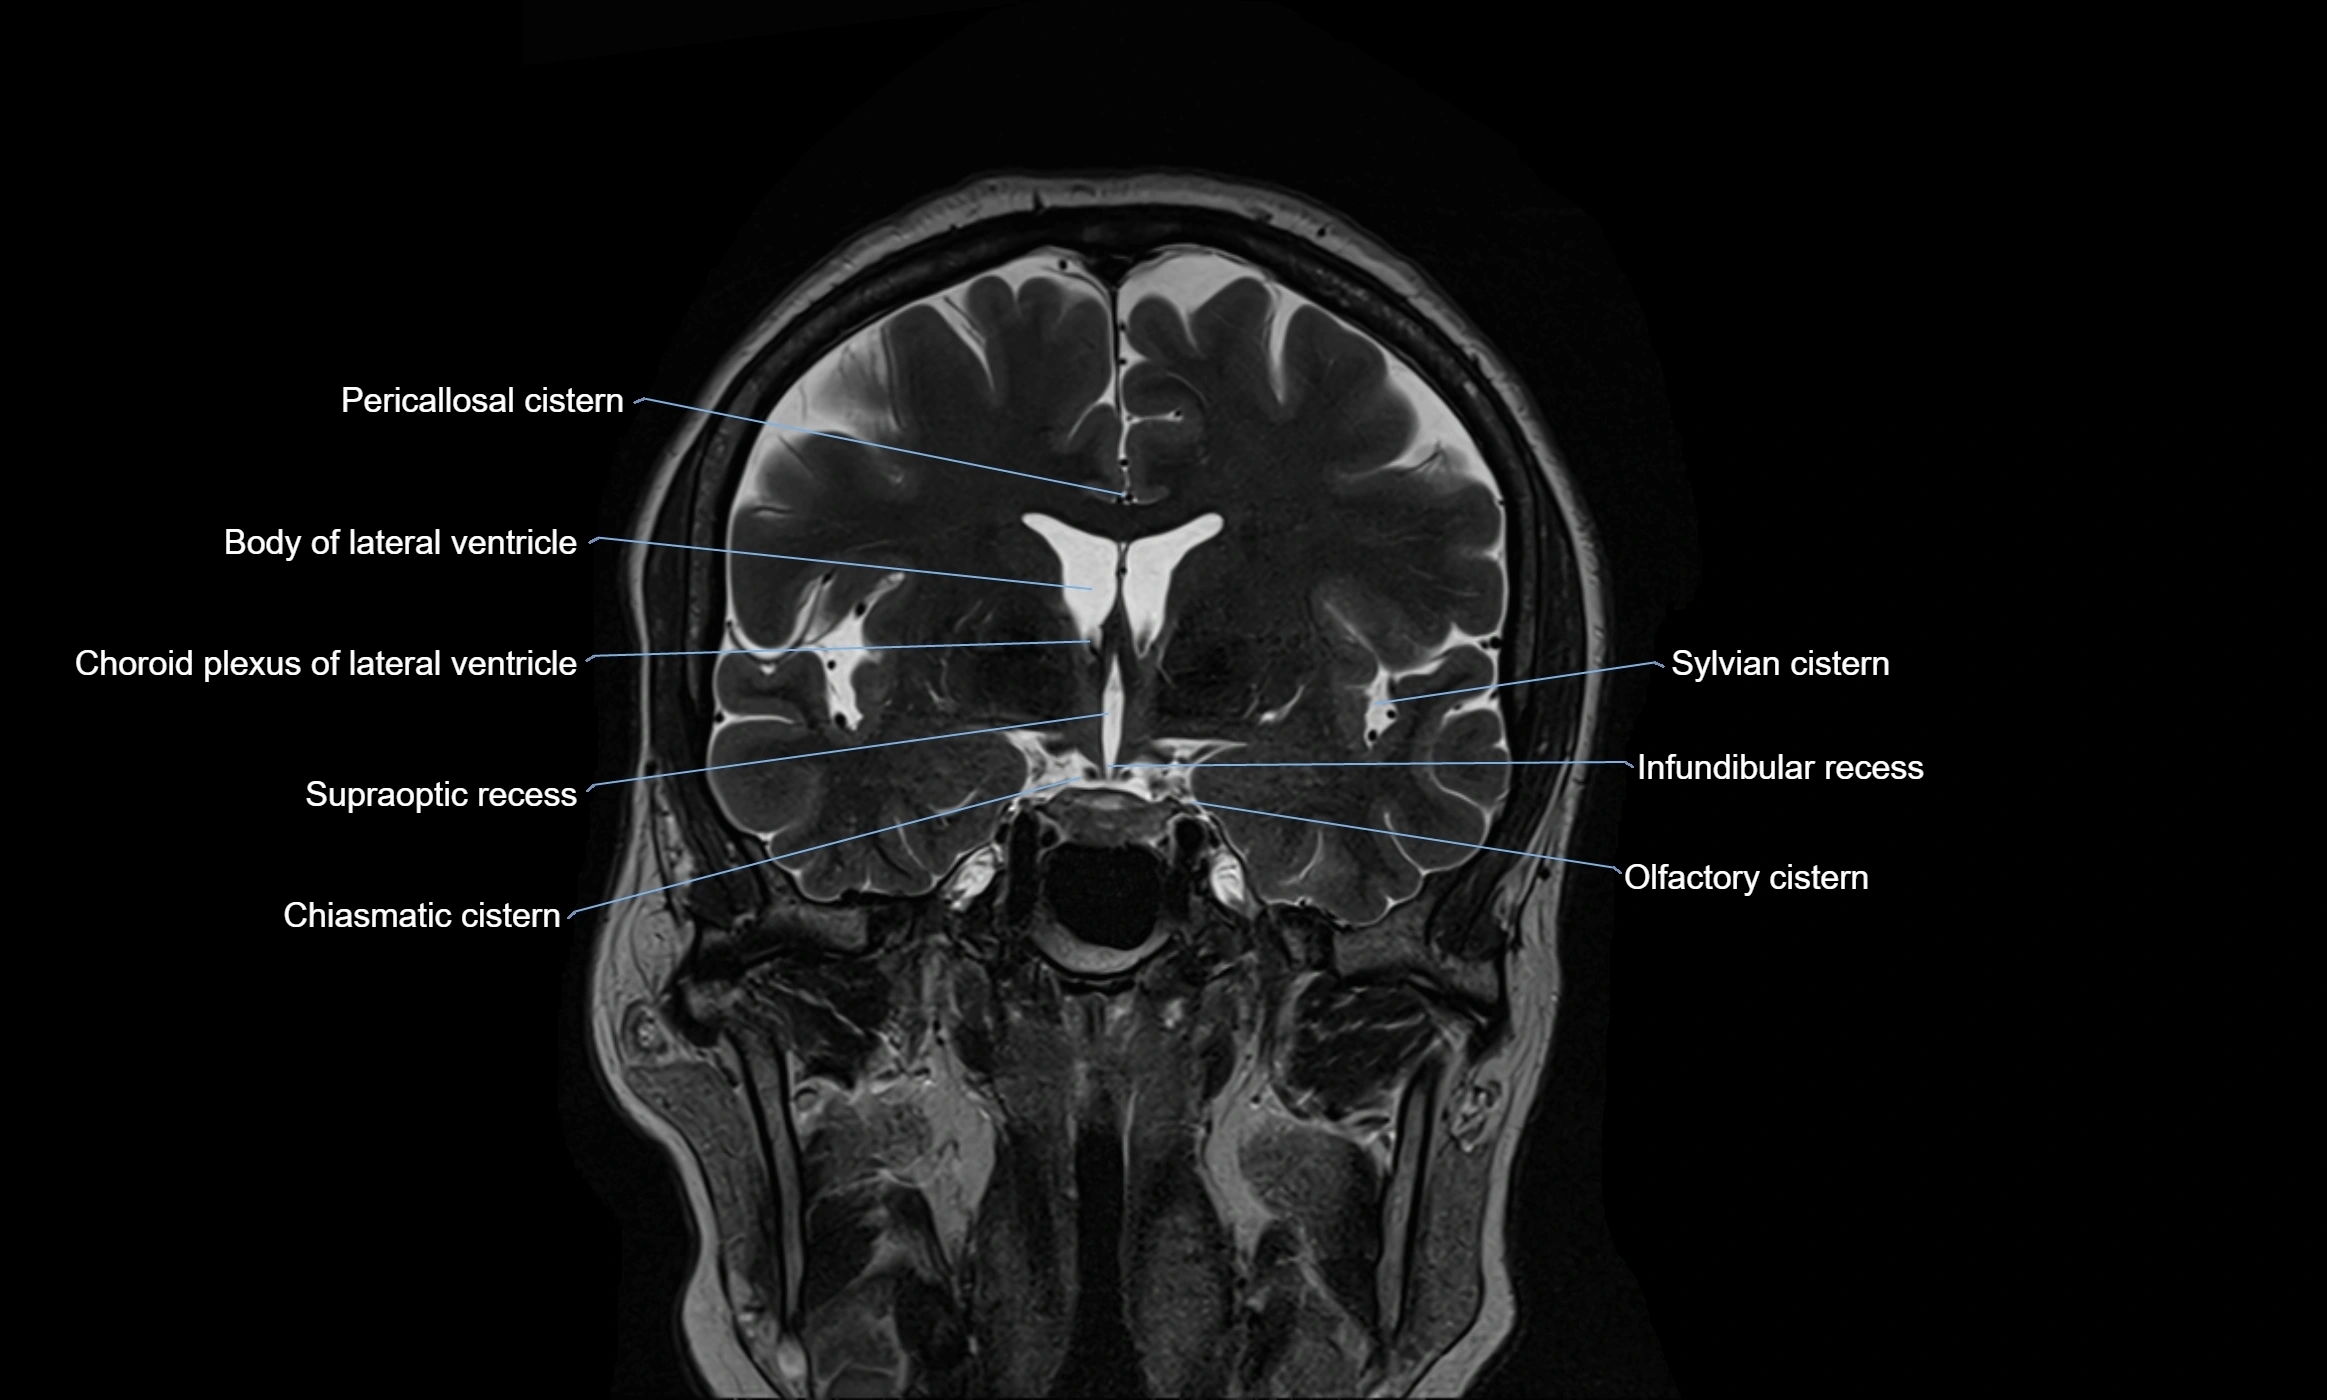

MRI images

image